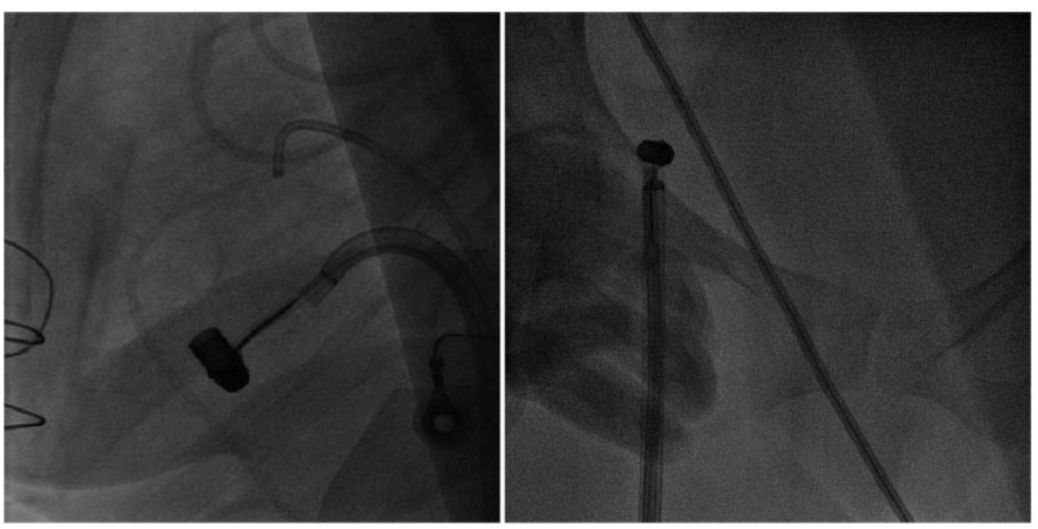

用套圈将*弹子**从外到内捕捉,以保证其适用于任何结构,如图3左;随后认真操作Agilis导管,并逆时针旋转到右心房。*弹子**进入右心房后,三尖瓣反流降低至轻度。在下腔静脉中,曾试图将整个组件与16-Fr结合,但最终以失败告终,因此将*弹子**拉至腹股沟,如图3右。

图3 左:*弹子**卡在右心室;右:用16-Fr鞘在右腹股沟捕获*弹子**

之后,*弹子**滑出向上移动到髂总静脉,并向下移动至右侧髂内静脉,如图4左。为了避免*弹子**滑脱,应在腹股沟*弹子**附近画一8字形缝合线。之后,选择由24-Fr鞘、JR 5-Fr引导管和15 mm的鹅颈管圈套组成的组件通过右侧股静脉,并在右侧股静脉内处理鹅颈管套圈。同时使用两个套圈捕捉*弹子**(图4右侧),并通过24-Fr鞘将*弹子**在右股静脉内安全取出,最终使用8号缝合线缝合静脉。

图4 左:*弹子**在套圈中滑脱,向上移动至右侧髂总静脉,之后又向下移动至右侧髂内静脉;右:两个股静脉套圈均捕获*弹子**